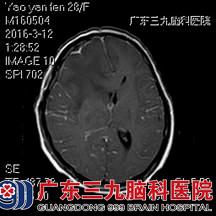

术后MR增强 出院时MR增强

术后姚女士的恢复情况良好,医生予抗感染、补液、营养神经等对症支持治疗;复查MR,显示右额叶及基底节区多发占位病变已切除,术后的病理诊断为脑脓肿。目前,姚女士神智清楚、精神状态良好、四肢可以自如活动。